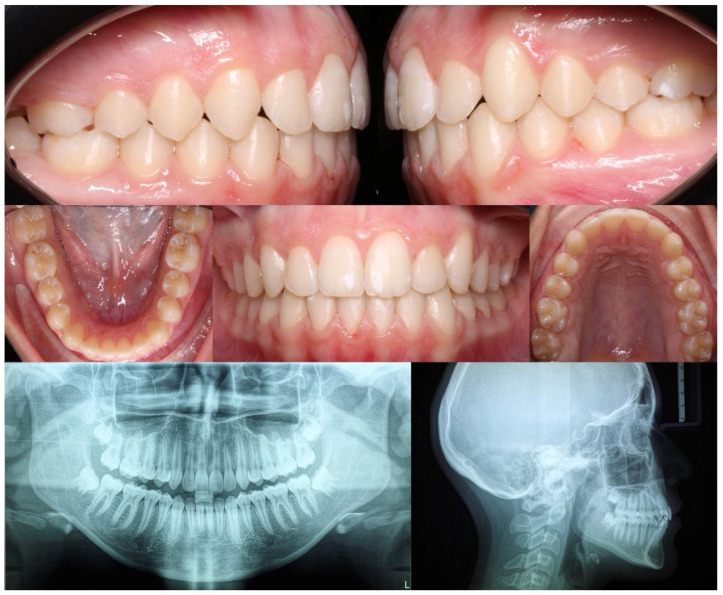

Background and Objectives: This study aimed to evaluate the outcomes of Class II subdivision teenage patients treated with Invisalign® clear aligners (CAs) and elastics. Materials and Methods: A total of 23 individuals aged 14.3 ± 2.5 years were enrolled in this study. The participants were divided into Group 1 (mandibular midline deviation) and Group 2 (maxillary midline deviation). The midline deviation from the facial midline; anteroposterior discrepancy; overjet (OJ), overbite (OB), and Peer Assessment Rating (PAR) scores; upper incisor and lower incisor (L1) positions; and angulation were measured at the beginning (T0) and end (T1) of the orthodontic treatment. Results: Group 1 showed significant higher variations in OJ (-2.3 ± 2.3 vs. -0.6 ± 0.8, p < 0.001), OB (-2.1 ± 2.3 vs. -1.1 ± 1.4, p < 0.001), PAR score (-32.0 ± 11.7 vs. -27.3 ± 13.1, p < 0.001), L1-to-mandibular-plane angle (-3.6 ± 7.0 vs. -1.3 ± 3.2, p < 0.001), and interincisal angle (10.07 ± 8.7 vs. 5.9 ± 5.3, p = 0.007). The midline deviation was the only measurement with higher variation in Group 2. The average distance between the mesiobuccal cusp of the maxillary first molar and the buccal groove of the mandibular first molar was 0.3 ± 0.5 mm. Conclusions: A total of 21 patients achieved bilateral Class I (91% success rate) and demonstrated great improvement (72-96%) in PAR scores. Regardless of the etiology of malocclusion, the orthodontic correction of the Class II subdivision with CAs showed high accuracy and predictable results.

Abstract Image